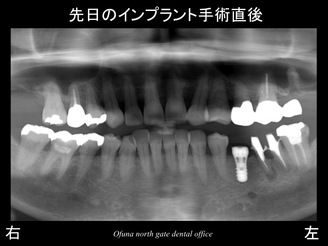

以下は、先日行った手術直後です。

使用したインプラントは、ストローマンインプラント(ITIインプラント) です。

骨吸収もほとんどなかったため、難しい治療ではありませんした。